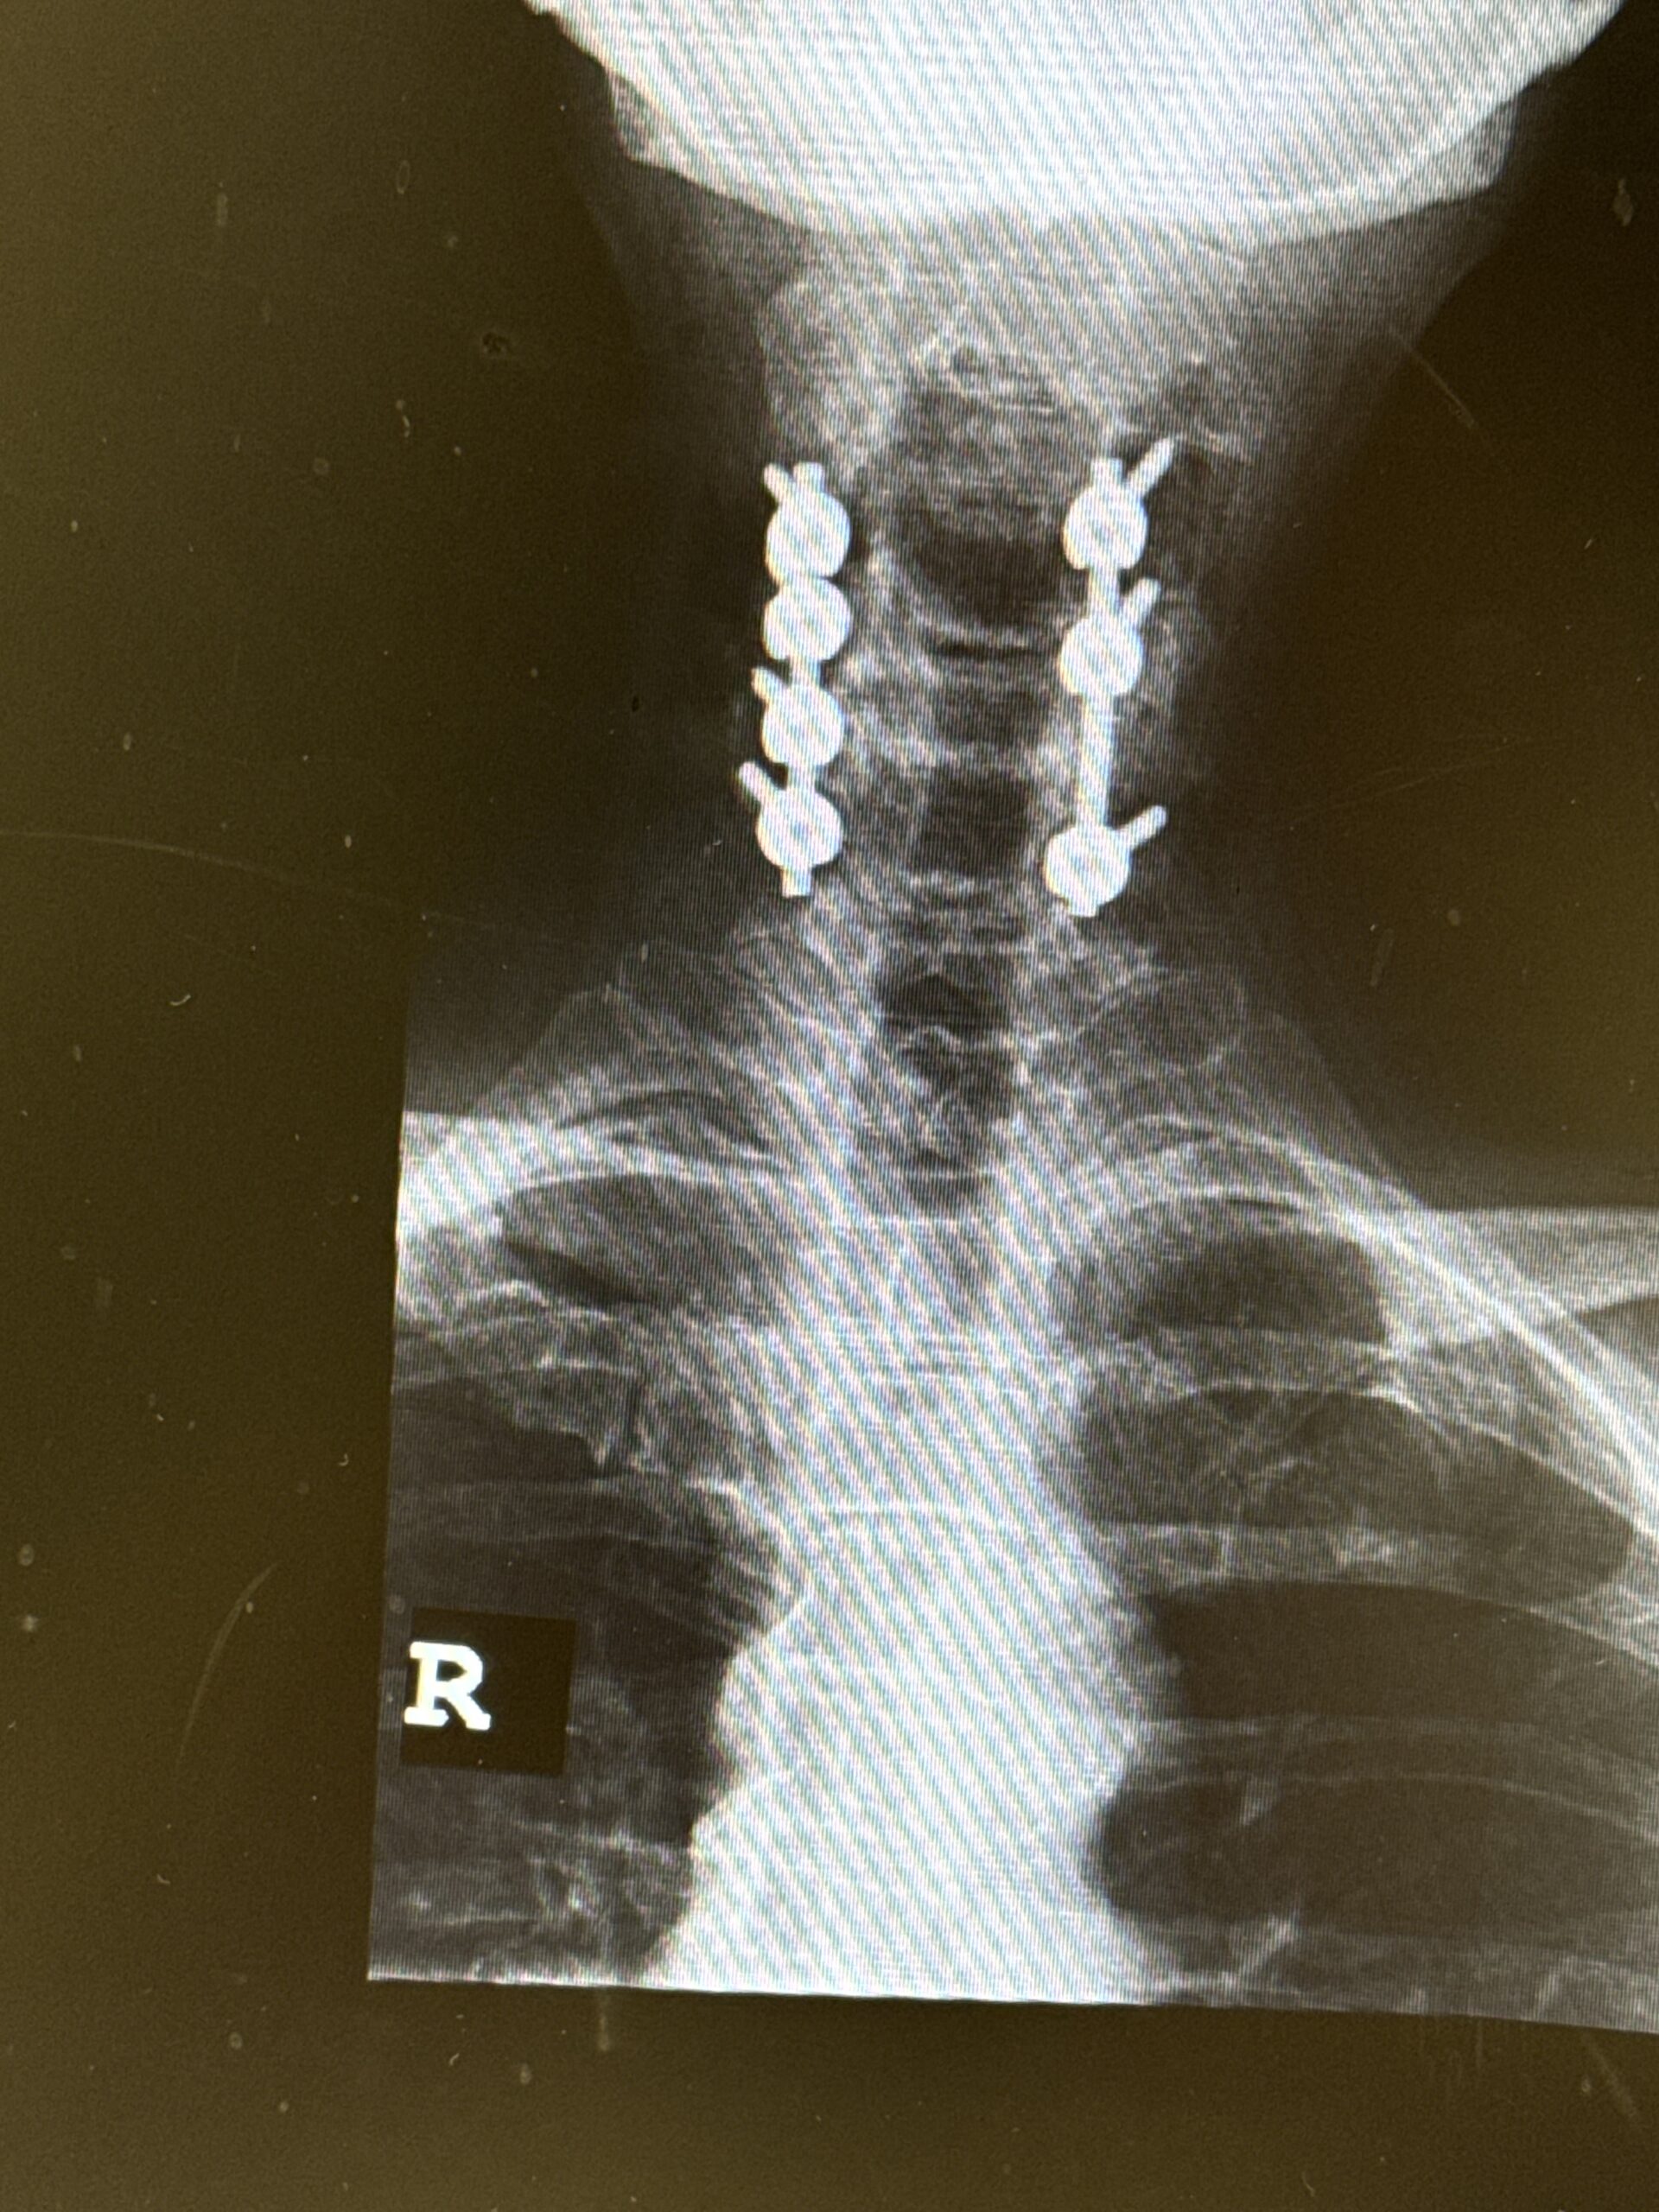

In this unique podcast, NSPC neurosurgeon Dr. William Sonstein and orthopedic spine surgeon Dr. Richard Obedian join forces to discuss a range of common spinal conditions. With their combined expertise, they explore issues such as spinal stenosis, herniated discs, cervical myelopathy, spondylolisthesis, and compression fractures. Their discussion is accessible and engaging, breaking down complex medical terms and treatments into clear, easy-to-understand explanations. Listeners will gain valuable insights into both surgeons’ approaches to diagnosis and treatment, offering practical advice and perspectives for patients and healthcare professionals alike.